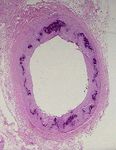

InsulinaLa Nefropatia Diabetica è quasi un «modello sperimentale» per testare l’effetto nefro-

protettivo dei farmaci bloccanti il R.A.S. Questi farmaci sono in grado di

ridurre la Pressione Idrostatica Intra-glomerulare contrastando l’ Iperfiltrazione

Glomerulare ed il passaggio di proteine attraverso la barriera glomerulare (Proteinuria)